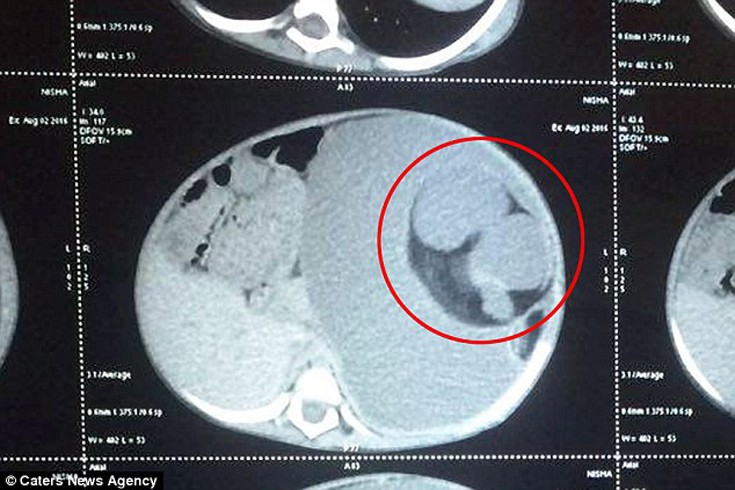

Ένα μωρό του οποίου το στομάχι ήταν τόσο πρησμένο που δεν μπορούσε να φάει ή να πιει τίποτα βρέθηκε με ένα «αγέννητο δίδυμο» μέσα του.

Οι γιατροί έμειναν έκπληκτοι όταν βρήκαν μια μάζα 3,5 κιλών από οστά, σάρκα και μαλλιά μέσα στην κοιλιά του μικρού κοριτσιού. Τελικά το μωρό διαγνώστηκε με μια σπάνια κατάσταση που μόνο 200 παρόμοιες καταστάσεις έχουν αναφερθεί ποτέ παγκοσμίως. Το «δίδυμο» τρεφόταν από το κοριτσάκι σχηματίζοντας κάτι σαν ομφάλιο λώρο, σύμφωνα με το δημοσίευμα της Daily Mail.

Αρχικά οι γιατροί πίστεψαν ότι επρόκειτο για μια μεγάλη κύστη ανακαλύπτοντας έκπληκτοι τι πραγματικά συνέβαινε. Στη συνέχεια, προχώρησαν άμεσα σε χειρουργική επέμβαση για να το αφαιρέσουν με τον παιδοχειρουργό να κάνει λόγο για έναν «όγκο που περιείχε ιστούς και όργανα». Τότε υποπτεύθηκε τι ακριβώς συνέβη και έψαξε σε βιβλιογραφίες για κάτι παρόμοιο. Όταν απομάκρυνε τον όγκο διαπίστωσε ότι επρόκειτο για έμβρυο. Η εγχείρηση η οποία κράτησε για δύο ώρες ήταν πολύ περίπλοκη καθώς το ένα νεφρό του κοριτσιού είχε κολλήσει πάνω στον όγκο.